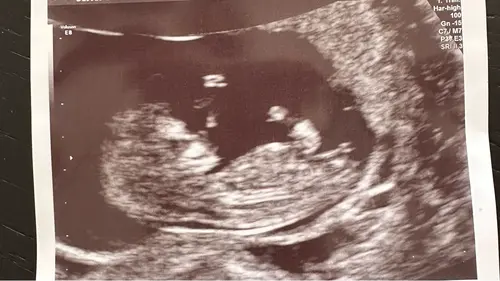

Meisje denk ik

Ik ben 11 weken al馃グ

Ik denk een meisje, en zo grappig het is net een z van slapen boven het hoofdje 馃槉

Jaaa meisje, maar eigenlijk is 11 weken te vroeg het zou ook nog kunnen stijgen en dan is het een jongen

Allebei is even welkom鉂わ笍 maar het zou wel super leuk zijn om nu een meisje te krijgen